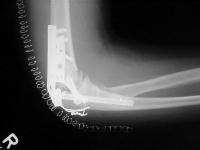

Finally, the titanium olecranon screw was replaced with a longer 6.5 mm stainless screw and tension band wire. Following this, the elbow was stabilized with an EBI hinged external fixator (not shown), planning to leave this on four weeks, anticipating inadvertent weight bearing due to the patient's bilateral calcaneal fractures.

Click for larger image